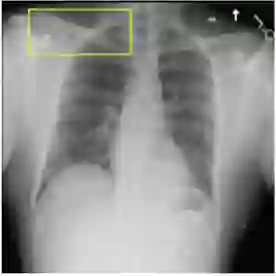

We introduce a novel Region-based contrastive pretraining for Medical Image Retrieval (RegionMIR) that demonstrates the feasibility of medical image retrieval with similar anatomical regions. RegionMIR addresses two major challenges for medical image retrieval i) standardization of clinically relevant searching criteria (e.g., anatomical, pathology-based), and ii) localization of anatomical area of interests that are semantically meaningful. In this work, we propose an ROI image retrieval image network that retrieves images with similar anatomy by extracting anatomical features (via bounding boxes) and evaluate similarity between pairwise anatomy-categorized features between the query and the database of images using contrastive learning. ROI queries are encoded using a contrastive-pretrained encoder that was fine-tuned for anatomy classification, which generates an anatomical-specific latent space for region-correlated image retrieval. During retrieval, we compare the anatomically encoded query to find similar features within a feature database generated from training samples, and retrieve images with similar regions from training samples. We evaluate our approach on both anatomy classification and image retrieval tasks using the Chest ImaGenome Dataset. Our proposed strategy yields an improvement over state-of-the-art pretraining and co-training strategies, from 92.24 to 94.12 (2.03%) classification accuracy in anatomies. We qualitatively evaluate the image retrieval performance demonstrating generalizability across multiple anatomies with different morphology.